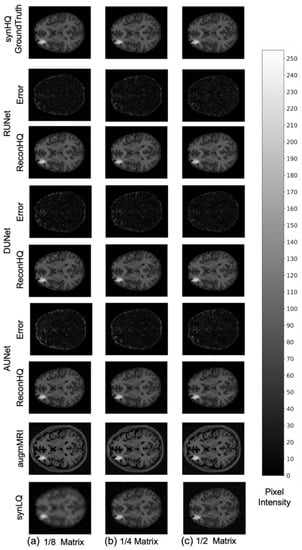

The performance of the UNets may also be appreciated in Figure 7 and Figure 8, which show the reconHQ images together with pixel-by-pixel differences with respect to the ground truth (i.e., |reconHQ—synHQ|) for the three networks at different synLQ sizes and two scanning scenarios. It can be observed that lesion reconstruction is better in the With-Prior compared to WithOut-Prior acquisition scenario for the 1/8 downsampled synLQ.

Figure 8.

Representative example of reconstructed images and errors versus ground truth with the three UNets trained for 100 epochs with the WithOut-Prior acquisition scenario (i.e., not including the augmMRI) to upscale (a) 1/8 downsampled (22 × 26) and (b) 1/4 downsampled (44 × 52) and (c) 1/2 downsampled (88 × 104) synLQ. The error intensity in this figure is three times the original intensity.